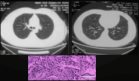

La vasculitis representa una complicación rara pero grave de la SoJIA, capaz de generar morbilidad significativa si no se identifica y trata de forma oportuna. En este caso, la vasculitis periférica condujo a gangrena digital, una manifestación infrecuente documentada en pocos reportes. Se presume que el proceso patológico implica la deposición de inmunocomplejos en las paredes vasculares, lo que genera inflamación, daño endotelial y posterior necrosis tisular.

El tratamiento inmunosupresor basado en corticosteroides y fármacos antirreumáticos modificadores de la enfermedad (FAME) resultó eficaz para controlar la inflamación sistémica. Sin embargo, una vez instaurada la gangrena, el manejo fue limitado a medidas quirúrgicas. La resolución temprana de la cianosis del pie derecho contrastó con la progresión de la necrosis en las manos, subrayando la relevancia del diagnóstico precoz y del tratamiento intensivo inicial.